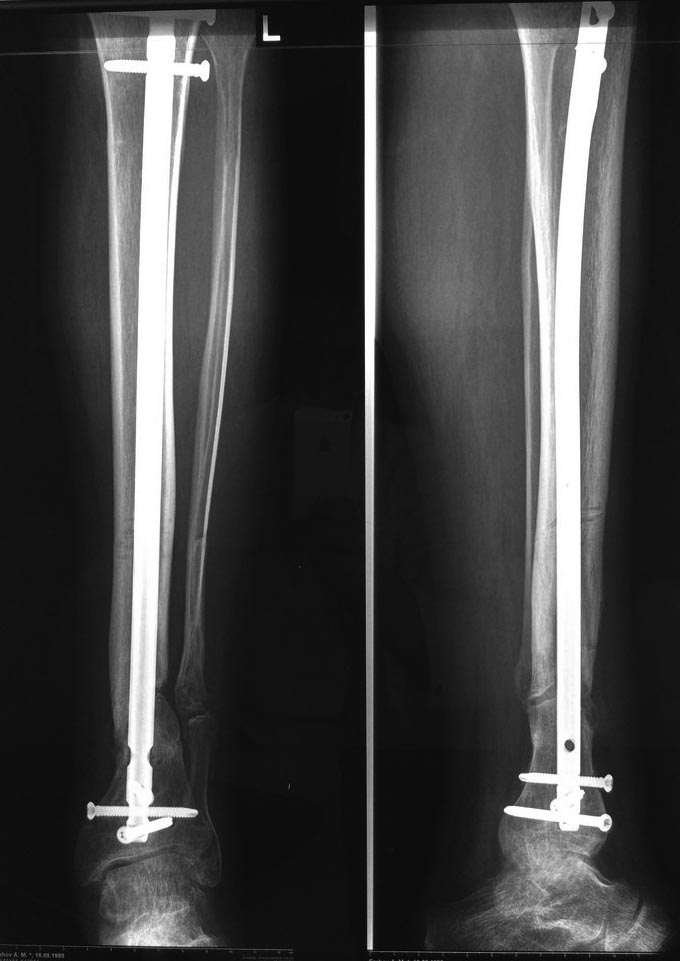

Уважаемые коллеги выразите Ваше мнение по следующему случаю.Молодой человек, 27 лет, находится на лечении с диагнозом: Ложный сустав большеберцовой кости в нижней трети, фиксированный интрамедуллярным блокированным стержнем (12.02.2014 г), ложный сустав малоберцовой кости в нижней трети левой голени, посттравматический артроз левого голеностопного сустава 1 стадии. Укорочение левой нижней конечности на 1,0 см. Со слов пациента известно, что в детстве получил перелом большеберцовой кости, лечился консервативно, перелом сросся с деформацией. Травма в июле 2010 г. бытовая-упал на лестнице, получил перелом малоберцовой кости, и перелом большеберцовой кости без смещения. Выполнена операция: Остеотомия большеберцовой кости в нижней трети, интрамедуллярный блокированный остеосинтез большеберцовой кости левой голени. Гладкое течение послеоперационного периода. Перелом большеберцовой кости сросся. Функция конечности восстановилась. В июне 2013 г выполнена операция удаление интрамедуллярного стержня из большеберцовой кости левой голени. Гладкое течение послеоперационного периода. Приступил к занятием физкультурой, бег. В августе 2013 г спрыгнул с автобуса, с чемоданом в руках, появилась резкая боль в левой голени. За медицинской помощью обратился через 7 дней, при обследовании выявлено: Рефрактура большеберцовой кости. Рекомендовано консервативное лечение в гипсовой повязке. В январе 2014 г. установлен диагноз: Ложный сустав большеберцовой кости в нижней трети, малоберцовой кости в нижней трети левой голени. Контрактура сгибательно - разгибательная левого голеностопного сустава. Посттравматический артроз левого голеностопного сустава 1 стадии. Укорочение левой нижней конечности на 1,0 см. В феврале 2014 г выполнил первым этапом: Фиксацию ложного сустава в АНФ с восстановлением осей сегментов. Через семь дней БИОС с рассверливанием. После операции - вальгус голеностопного сустава. Гладкое течение послеоперационного периода. Нагрузка по переносимости боли. Через 6 недель динамизация, через 2 недели стали мигрировать 2 фронтальных винта. Пытался подкрутить, пришлось удалить. Через 6 мес., контроль - линия ложного сустава прослеживается, но имеется периостальная костная мозоль. Не хватает стабильности.Вопрос что делать?Вариант № 1- выполнить реостеосинтез с рассверливанием КМК и на 12 мм диаметра гвоздь (стоит 11 мм)и убрать ротацию стопы руками одномоментно или одномоментно при помощи АНФ во время операции. Вариант № 2 выполнить удаление гвоздя, сделать все то же, что 6 месяцев назад, но с восстановлением анатомических взаимоотношений в голеностопном суставе.Вариант № 3 Двухэтапно, вторым этапом пластина на большеберцовую кость + костная пластика области не сращения.Вариант № 4 удаление гвоздя и лечение в КДА. Вопросы:1. Какой вариант оперативного лечения будет оптимальным в данном случае.2. При двухэтапной методике в дистальном отломке имеется канал от гвоздя, как направить гвоздь к наружному отделу дистального отломка большеберцовой кости. Есть опасения, что гвоздик может пойти по тому же каналу. Использовать поллер спицы или винты – сработают ли? И достаточна ли будет жесткость фиксации дистального отломка большеберцовой кости на гвоздике при 3 – 4 винтах при реостеосинтезе гвоздем.3. Нужен ли остеосинтез малоберцовой кости в нижней трети, с целью создания латеральной опоры. К сообществу за советом.

Здесь можно использовать все названные варианты. Гвоздь вполне тоже можно. Надо аппаратом восстановить длину и не повторять прежней ошибки - надо латеральную стенку сопоставить, а не оставлять наружного смещения. Да, надо ввести передне-задние спицы, чтобы не дать стержню попасть в старый канал. И длинной ручной разверткой лучше бы сформировать новый канал.

Возможно, не все снимки выставлены, потому что не нашел признаков проведенной динамизации, о которой писали. Верхние винты остались нетронутыми, трудно опознать динамизацию. По поводу применения “cap” на гвозде имеется сомнение, потому что высоко расположенный по верхнему краю гвоздь не позволяет воспроизвести динамизацию. Перед динамизацией надо укорачивать гвоздь или убирать “кап”.

По поводу лечения, проблем правильной установки гвоздя не будет. Можно с помощью поллеров, которые помогут вывести в нужную траекторию. Но, если прежние попытки не привели к успеху, стоит ли тогда повторить неудачный опыт? Какая гарантия, что вальгусные силы не деформирует ось. Надо пересмотреть иллюзию, что гвоздь является идеальным фиксатором для решения данной патологии! Еще, при попытке подвести проблему под определенный фиксатор, результат получается неутешительным!

Из предложенных, я бы остановился на третьем варианте. Основная работа должна быть против вальгуса, и медиальная пластина для этой роли не подходит. Передний доступ, остеотомия большой и малоберцовой. Сагиттальная пила для артропластики толстая и не экономит кость. Полотно не более, чем 1.1 мм толщиной, создает идеальную поверхность остеотомии. Затем боковая компрессия-лагированием и передная пластина с костным графтом! Возможно, потеряет часть высоты, но наконец то возникнет сращение!